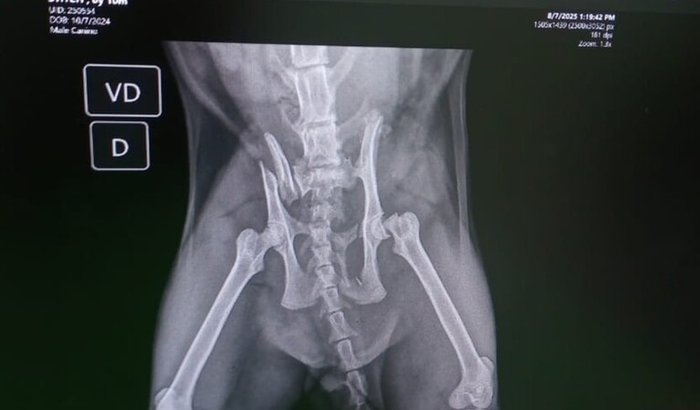

Ola me chamo Luciana e sou mãe do Stitch ,um filhote aventureiro que só tenho apenas 10 meses,uma dessas aventuras dele , infelizmente ele foi atropelado e que custo uma fratura no fêmur e fratura de ileo.Tentamos no particular e tudo sair um valor de 6.430,00 ,fomos no público e ele estão com agenda lotadas e sem previsão e as fratura do Stitch pode perfura umas das artérias dele.Estamos correndo contra o tempo.Quem puder nos ajudar.